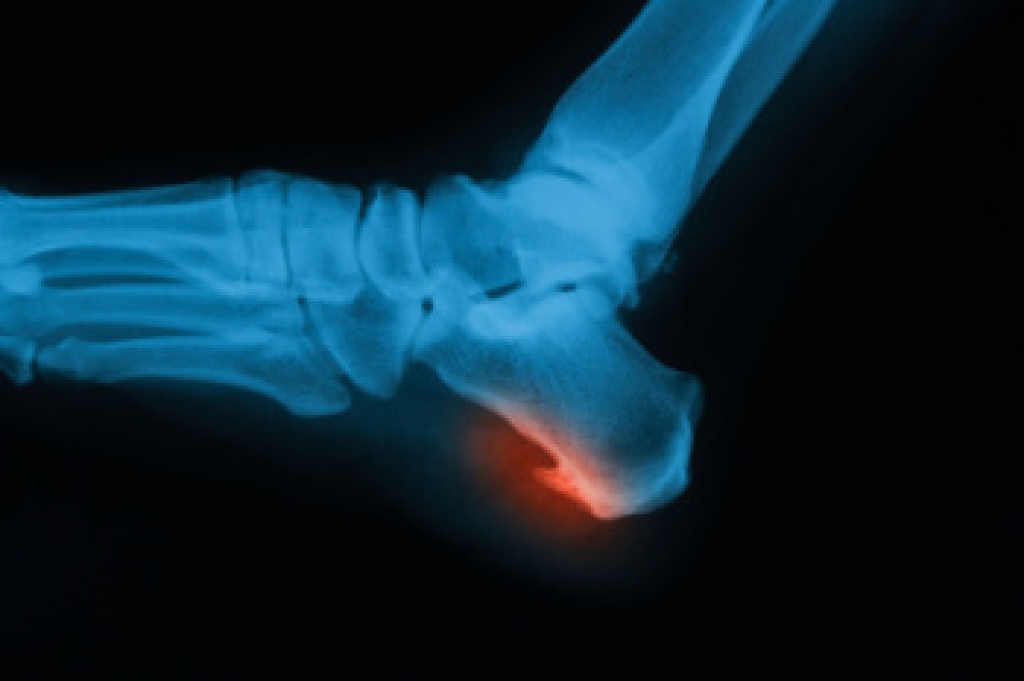

Morton's neuroma is a painful foot condition that commonly affects the areas between the second and third or third and fourth toe, although other areas of the foot are also susceptible. Morton’s neuroma is caused by an inflamed nerve in the foot that is being squeezed and aggravated by surrounding bones.